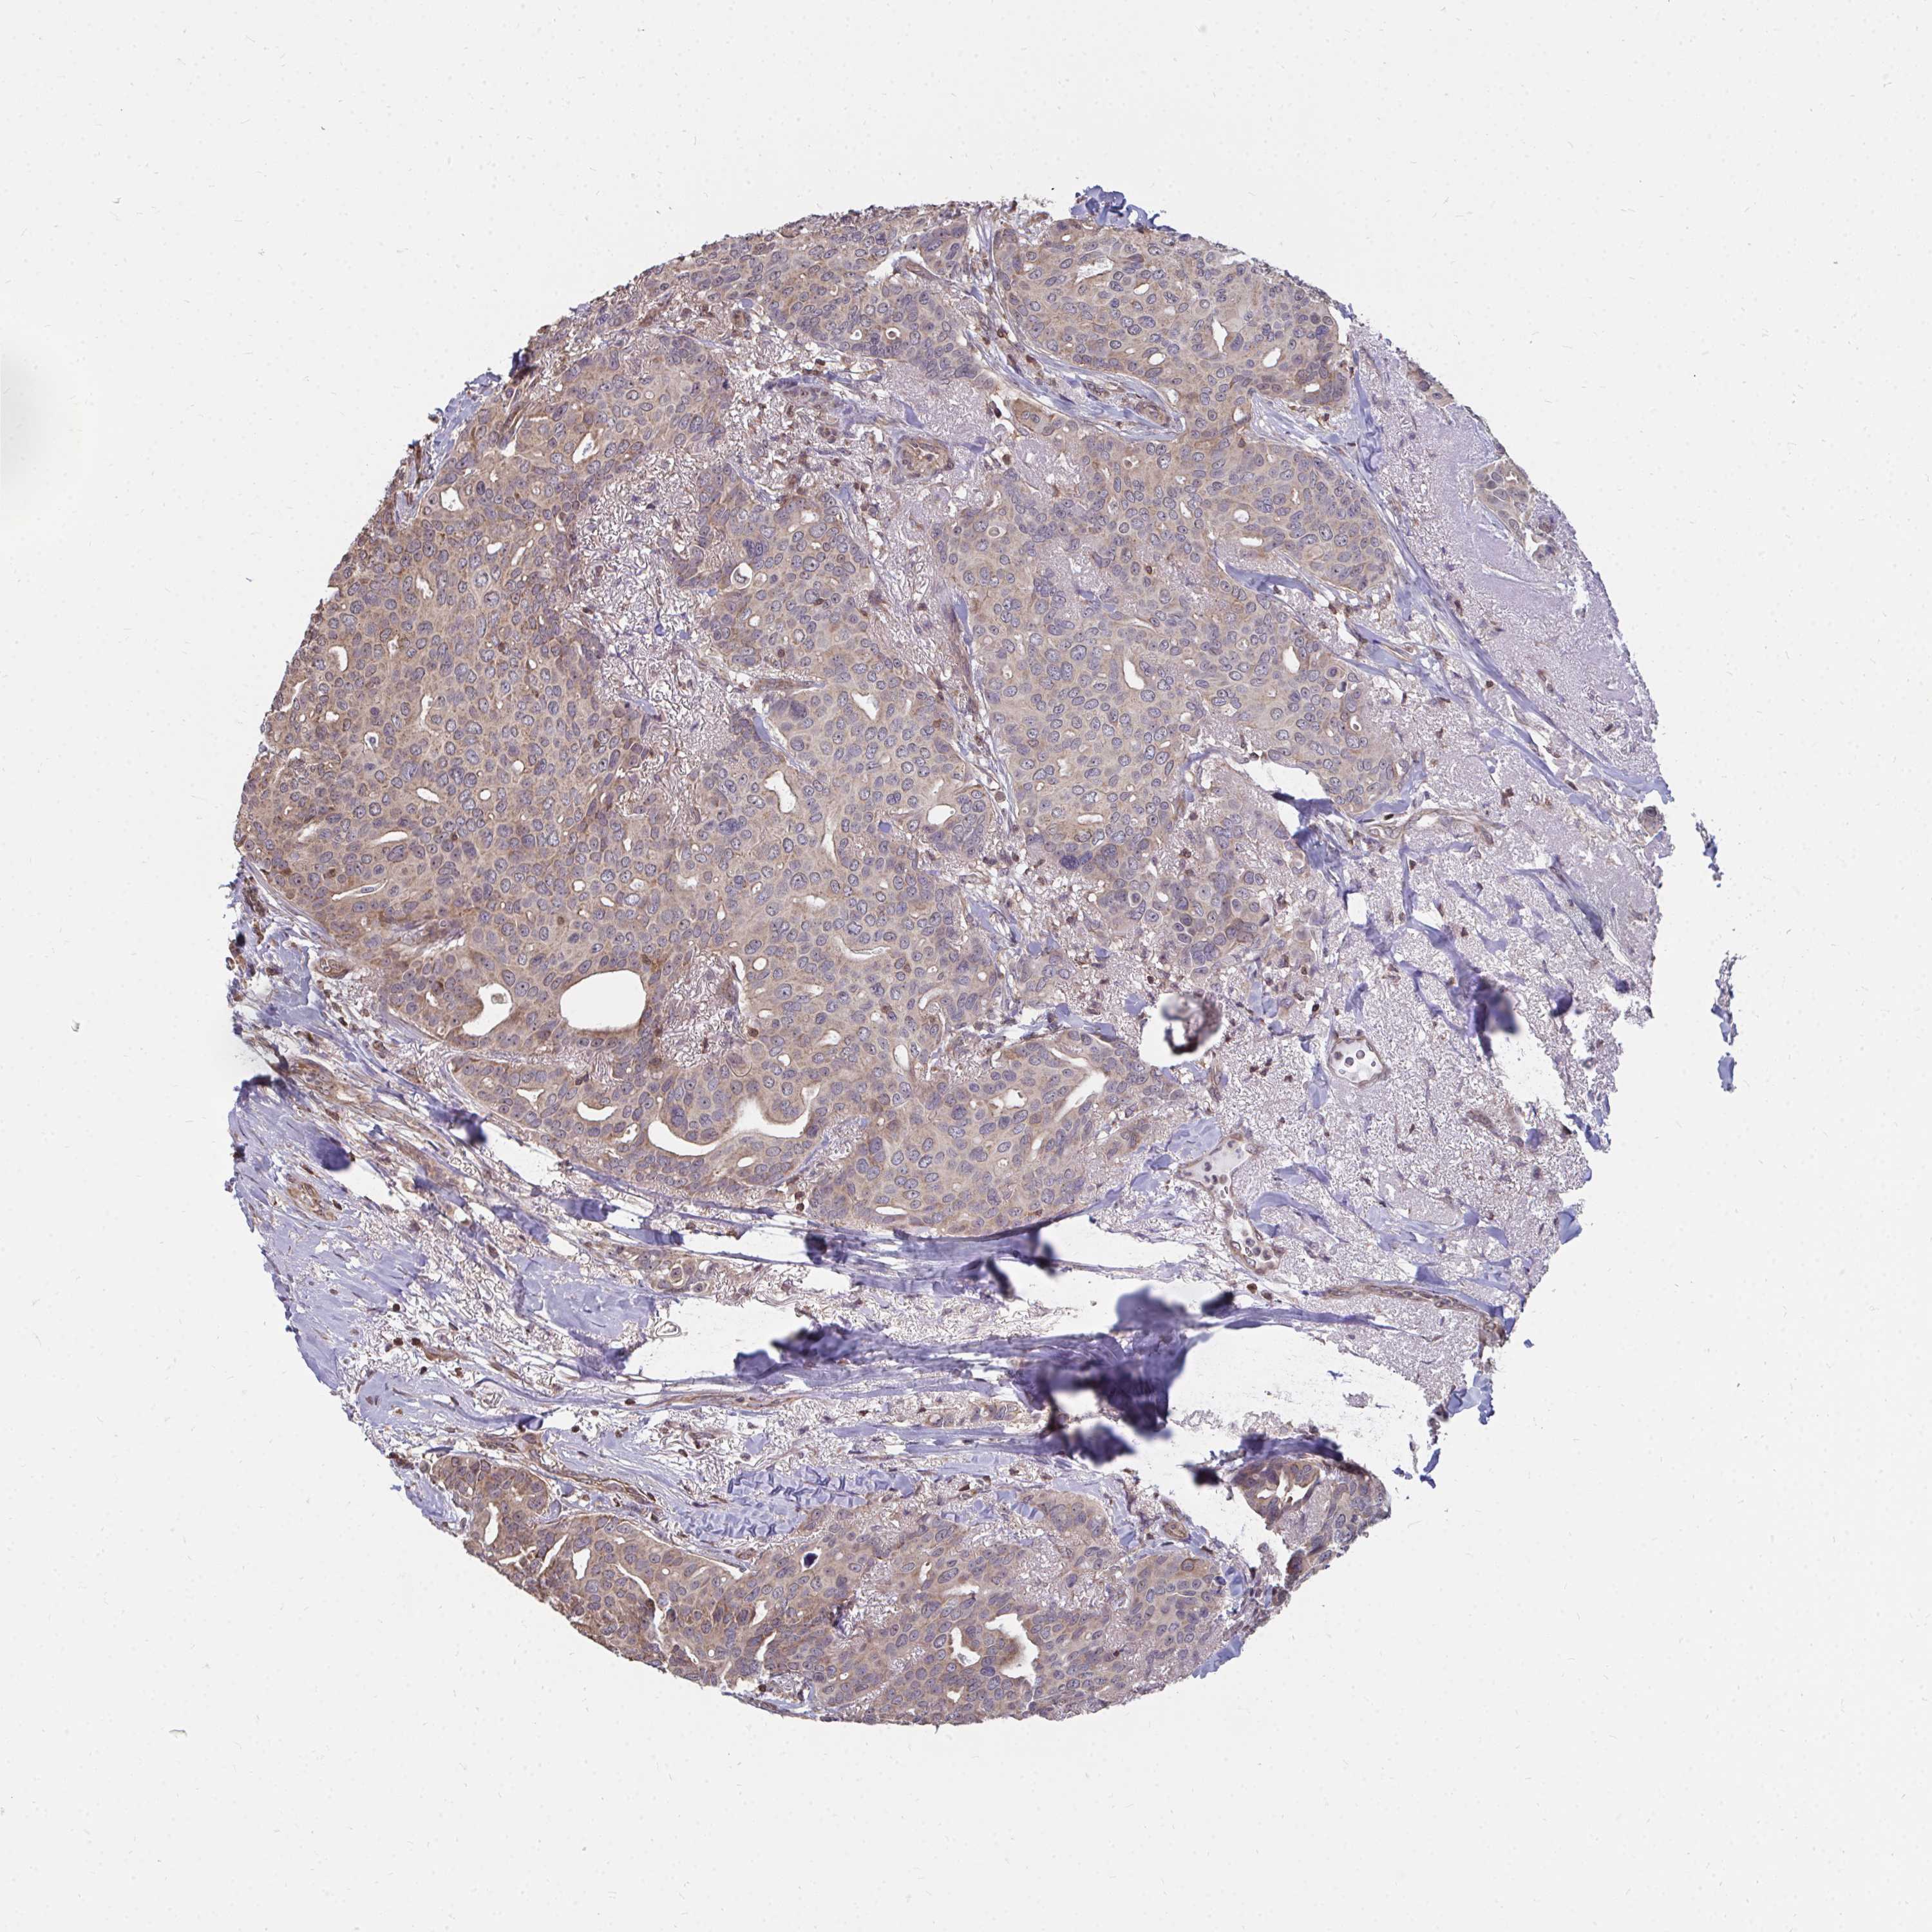

CANCER BREAST CANCER Show tissue menu

BRCA TCGA BRCA VALIDATION PROTEIN EXPRESSION

Breast cancer

Human cancer

Breast invasive carcinoma